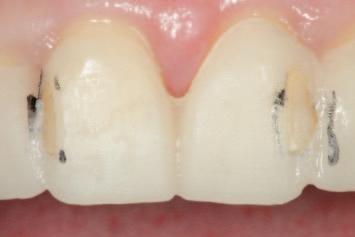

n Before initiating tooth preparation with diamond burs under copious water coolant, highly visible contrasting marks should be applied to the window perimeter of the preparation guide adjacent to the identified areas of

interference (Figure 3). These visual cues enhance intra-operative visibility and reduce the risk of over-preparation, which can occur when the guide’s reference contours are obscured by the coolant spray.

n Tooth structure is reduced until it conforms precisely to the contours of the preparation guide. The removal of the contrasting marker ink, caused by direct contact with the rotating diamond bur, indicates that the target reduction depth has been achieved. This visual endpoint ensures accurate, conservative preparation aligned with the contours of the planned definitive

(

restoration

Figure 4).

FIGURE 3: Pre-operative marking of the preparation guide with a visually contrasting colour prior to tooth reduction.

A C B

FIGURE 4: The appearance of the guide following the tooth reduction procedure. The clinician should stop the procedure the moment the contrasting ink has been displaced.